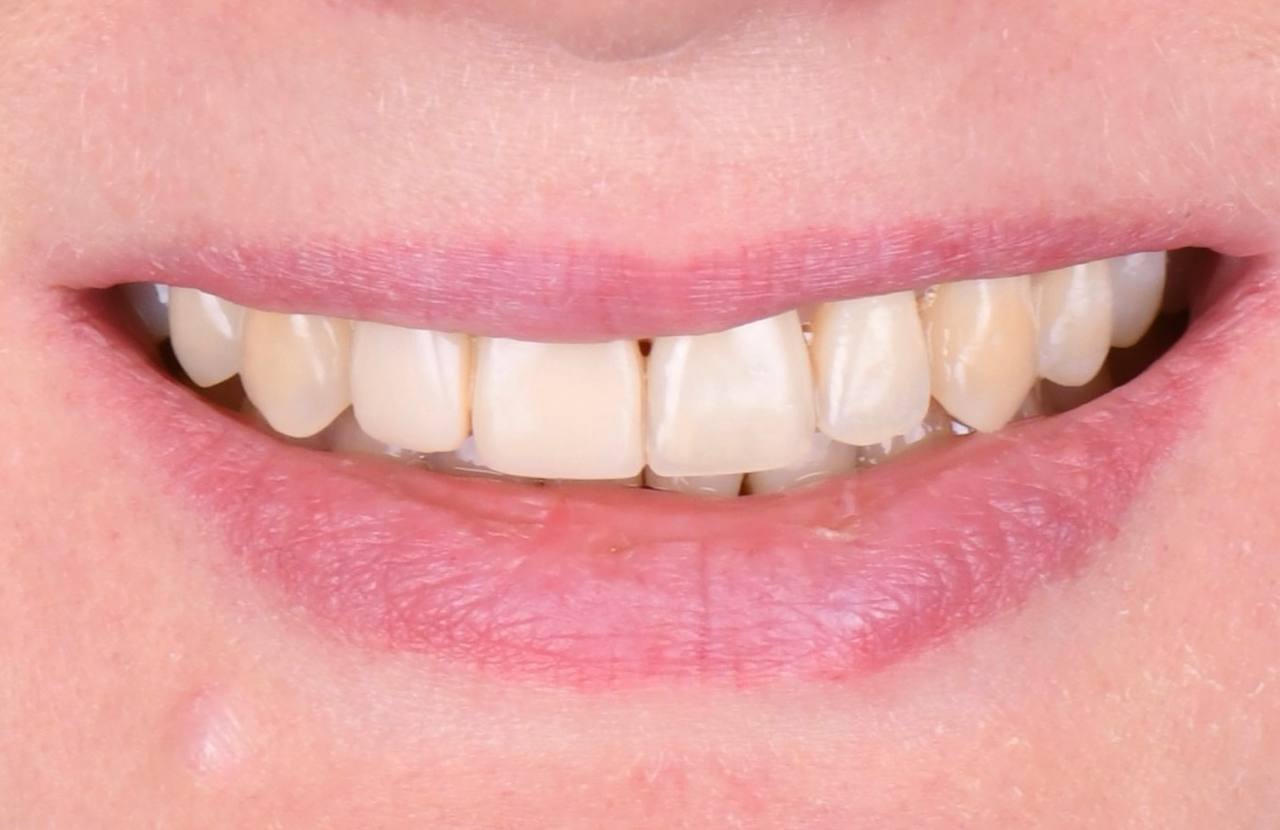

Я всегда мечтала закрыть промежуток между передними зубами. Бесконечно счастлива, что пришла в клинику ОК и мне здесь помогли. Егор Иванович провел ювелирную работу: отбеливание и реставрацию зубов. Теперь я улыбаюсь, не стесняясь!

Очень хотела убрать скол между зубами и мечтала о красивой улыбке. Реставрация спасла меня. Благодарю клинику и Егора Ивановича за проделанную работу!

Прекрасно справились с моей задачей по улучшению улыбки. Сделала керамические виниры и готова теперь улыбаться постоянно

В детстве я упал и сломал передний зуб. Тогда мне сделали пломбу. Уже после ортодонтического лечения была проведена реставрация этого зуба. Теперь я очень доволен результатом работы! Спасибо!